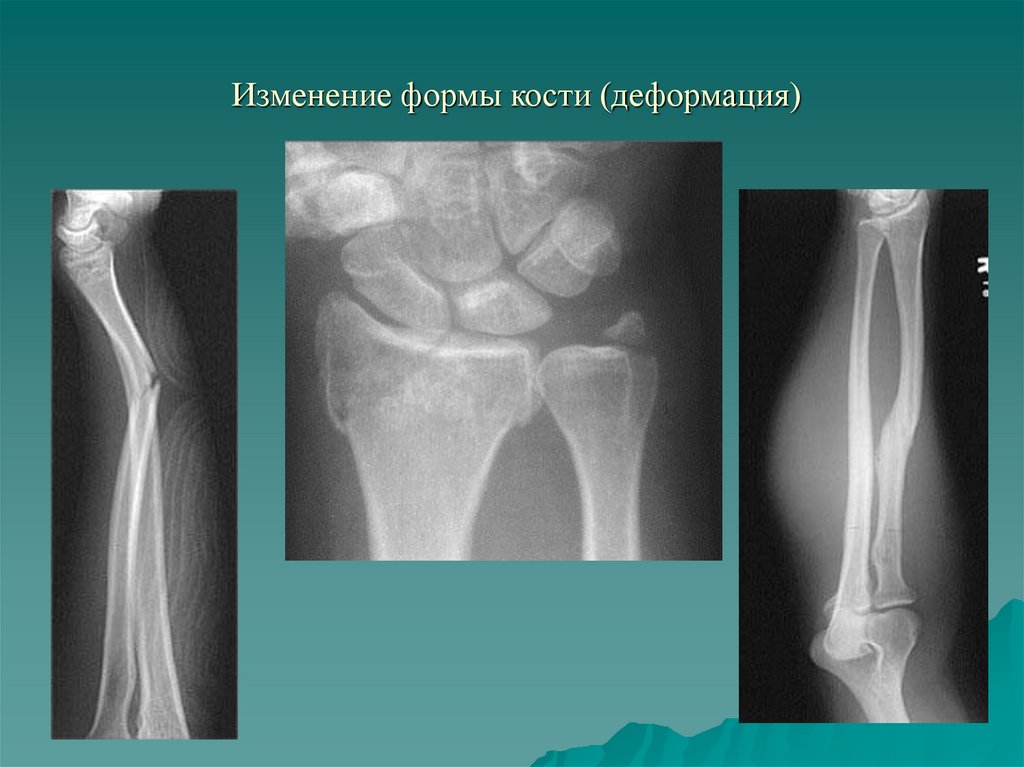

16.

1.6. Деформация кости

Тотальные или частичные

послеоперационные,

травматические дефекты;

- Изменение оси кости (острая

травма, посттравматические

деформации; врожденная

патология, обменные нарушения);

- Изменение формы суставных

поверхностей (травма, воспаление,

дегенеративные процессы,

опухоль)

17. Изменение формы кости (деформация)